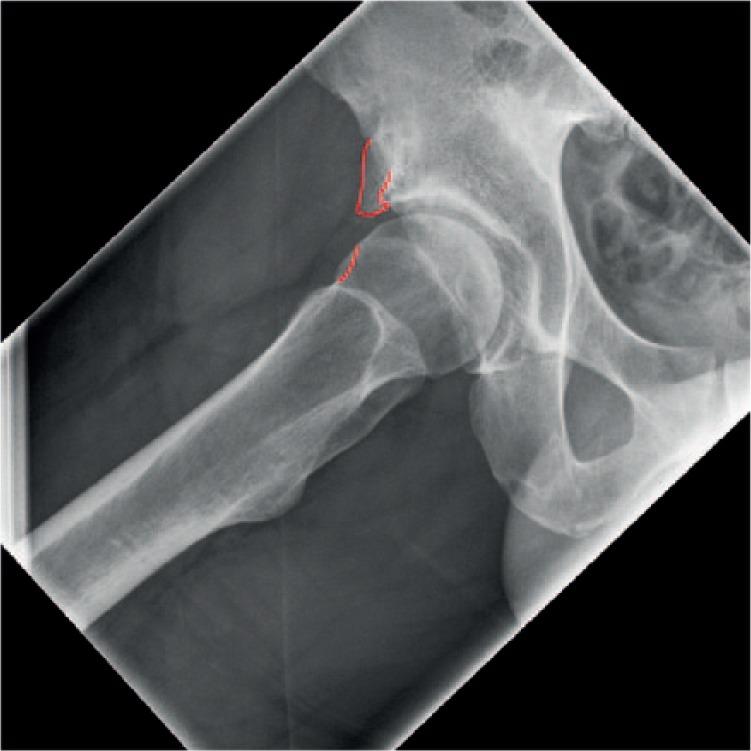

In this review, we bring to the attention of the reader three relatively unknown types of hip impingement. We explain the concept of low anterior inferior iliac spine (AIIS) impingement, also known as sub-spine impingement, ischio-femoral impingement (IFI) and pelvi-trochanteric impingement. For each type of impingement, we performed a search of relevant literature.We searched the PubMed, Medline (Ovid) and Embase databases from 1960 to March 2016. For each different type of impingement, a different search strategy was conducted.In total, 19 studies were included and described. No data analysis was performed since there was not much comparable data between studies.An overview of symptoms, clinical tests and possible surgical treatment options for the three different types of extra-articular impingement is provided.Several disorders around the hip can cause similar complaints. Therefore, we plead for a standardized classification. In young and athletic patients, in particular, there is much to gain if hip impingement is diagnosed early. Cite this article: 2018;3:30-38. DOI: 10.1302/2058-5241.3.160068.